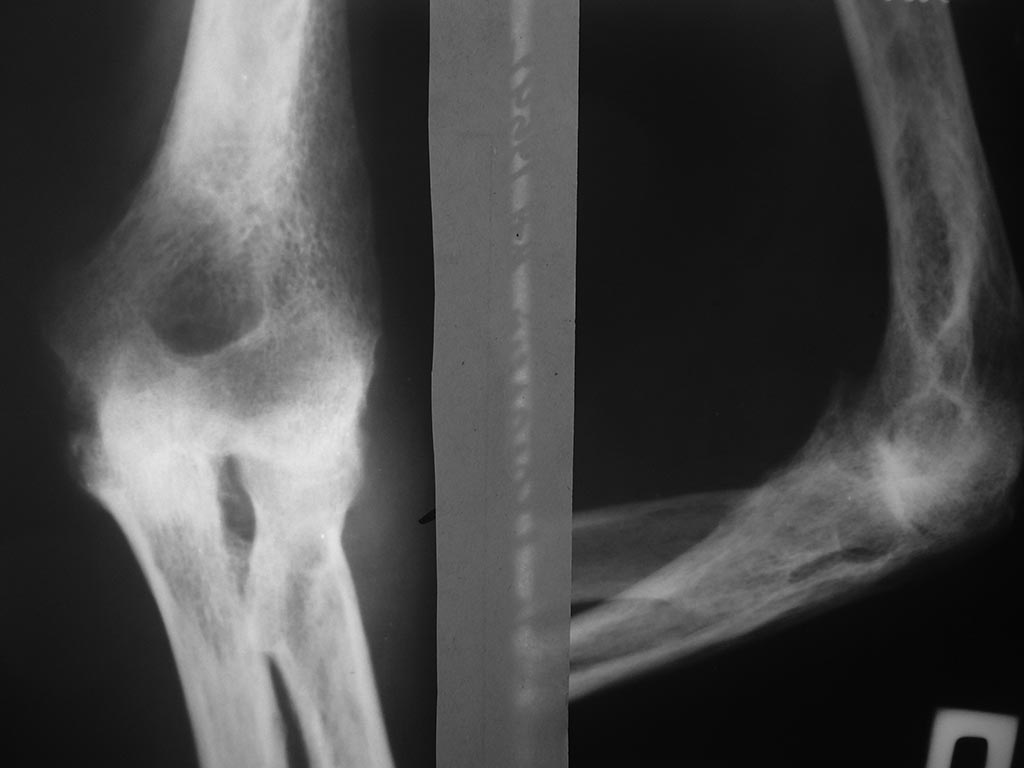

Уважаемые коллеги! Прошу подсказать клинику вна Украине занимающуюся

протезированием локтевого сустава.Больному 61 год. Бывший

профессиональный гимнаст.